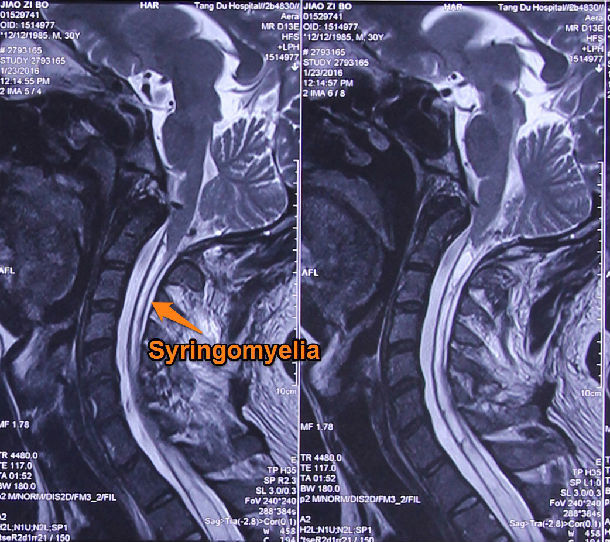

音频病例点评脊髓空洞症

图片尺寸640x789